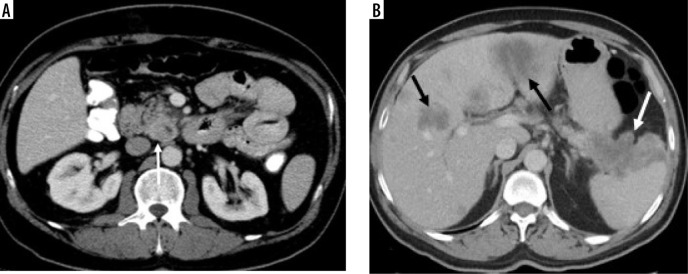

Results: There was no difference between the groups in terms of age, gender, tumour localisation, and internal structure (p = 0.23, p = 0.81, p = 0.19, and p = 0.94, respectively). Qualitative features significantly differed in terms of tumour margin feature, visual tumour density, presence of cystic component, and presence of necrosis (p = 0.01, p = 0.0001, p = 0.002, and p = 0.004, respectively). Tumour size, Tmden, Tmden/VPden, and Tmden/PanPden showed differences between groups (p = 0.0001, p = 0.002, p = 0.0001, p = 0.0001, respectively). The presence of cystic density in PDAC patients differed according to grade (p = 0.01).

Conclusions: While ill-defined irregular margins, hypodense visual tumour density, no cystic component, low value of Tmden, and low ratios of Tmden/VPden and Tmden/PanPden indicate PDAC, regular margins, iso-or hyperdense visual tumour density, cystic component, high value of Tmden, and high ratios of Tmden/VPden and Tmden/PanPden indicate PNET. SC can be differentiated from them by containing necrosis and reaching larger sizes. The presence of a cystic component in PDAC patients indicates high grade.